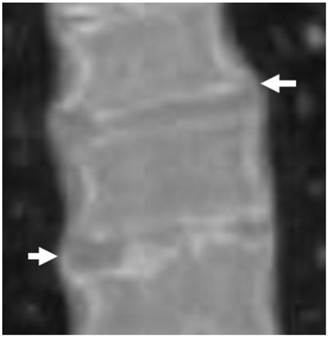

3D reformatted coronal CT scanning in a 15-year-old girl showed extensive hyperostosis of the anterior longitudinal spinal ligaments, resulting in the characteristic radiographic finding of a Bamboo-like spine resembling ankylosing spondylitis, the overall spine pathology is compatible with severe premature spine degeneration overwhelmed by diffuse hyperostosis (fig 3).

Fig 3

3D reformatted coronal CT scanning in a 15-year-old girl showed extensive hyperostosis of the anterior longitudinal spinal ligaments, resulting in the characteristic radiographic finding of a Bamboo-like spine resembling ankylosing spondylitis, the overall spine pathology is compatible with severe premature spine degeneration overwhelmed by diffuse hyperostosis (arrows).